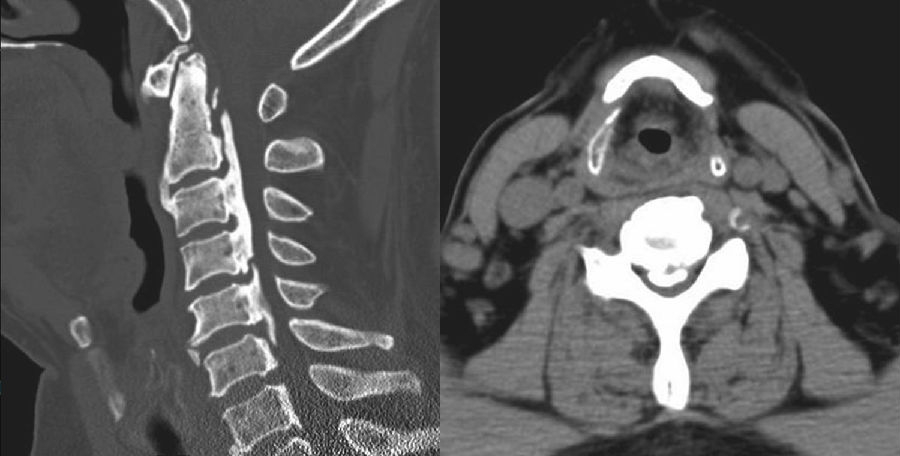

术前CT检查提示颈椎生理曲度变直,C1-7椎体边缘骨质变尖,寰枢间隙变窄(图1左)。C2-6段后纵韧带可见条形骨质密度影,C2-6段椎管有效前后径变窄,最窄处前后径约4mm(图1右)。寰枢关节周围韧带、C2-3段及C5-6段前纵韧带区可见条片状致密影。

图1 术前CT矢状位示颈椎生理曲度变直,后纵韧带钙化明显;

术前CT轴位示椎管前后径变小

该病例从术前CT看OPLL严重程度超过椎管横径2/3(图1右),我们首先选择了后路C2-6去椎板减压和侧块内固定术(图2),术后患者四肢肌力改善,神经功能症状得以改善。从术后磁共振(MRI)看(图4),尽管OPLL对脊髓的压迫来自前方,但后路去椎板减压和侧块内固定后,脊髓前方蛛网膜下腔有所改善且明显增宽。术后四肢运动功能改善良好,但患者仍存在C5-6神经根轴位受压和牵拉的疼痛症状,分析确定后,再行C4-6前路ACCF减压。我们对该严重OPLL病例,通过先后路减压+固定的方法,再行前路部分节段减压+固定的方法,既降低了严重OPLL减压手术的风险,又提高了治疗效果。